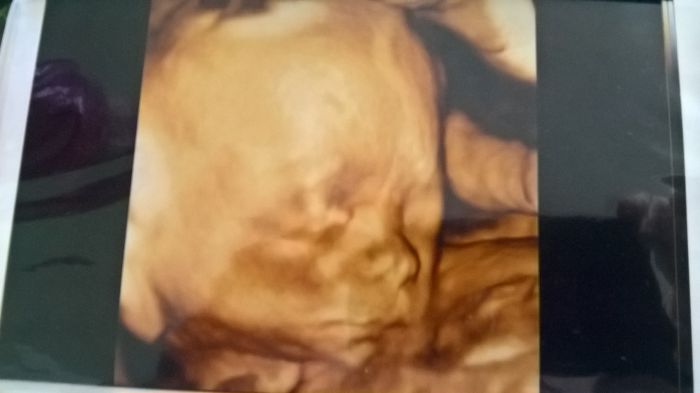

[1124278]Tak to je super. A máte i krásnou fotecku

Krásná fotwxka Lentilko

Lentilko super a krásná fotečka!